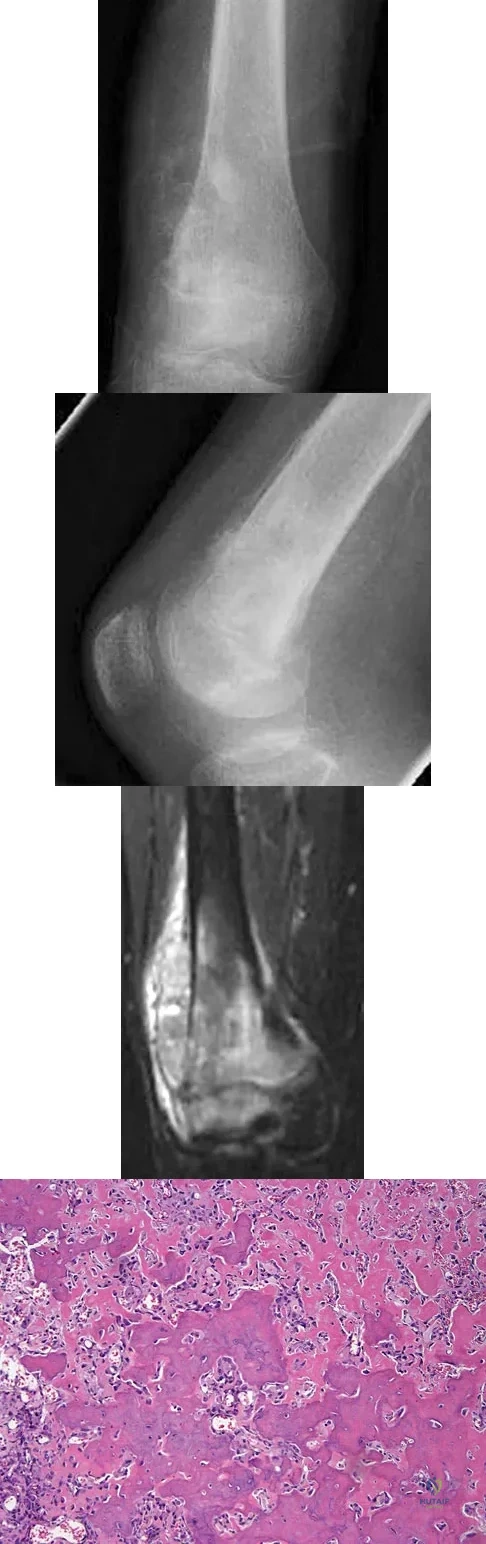

A 13-year-old girl has had increasing left hip pain for the past 4 months. A radiograph, bone scan, MRI scan, and photomicrograph are shown in Figures 1a through 1d. Which of the following immunohistochemistry results would confirm the most likely diagnosis?

Explanation

A healthy 16-year-old boy has had increasing pain in the right knee for the past 3 months. Examination reveals warmth and swelling around the distal femur. Radiographs and an MRI scan are shown in Figures 51a through 51c, and a biopsy specimen is shown in Figure 51d. What is the most likely diagnosis?

Explanation